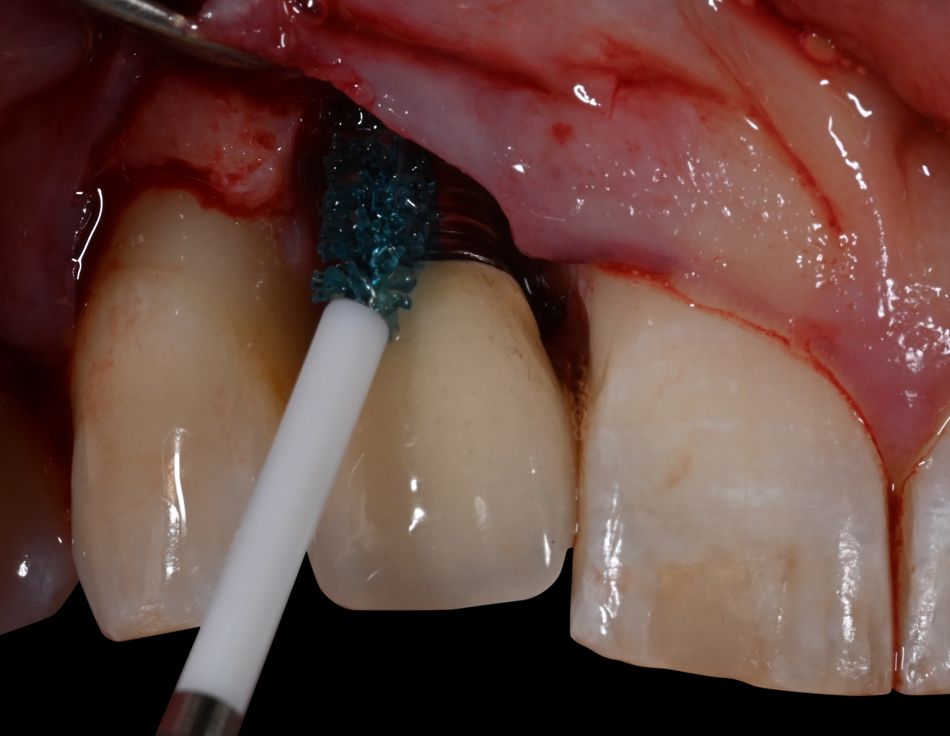

After local anesthesia with Xylocaine Dental Adrenaline (Xylocaine 20 mg/ml + epinephrine 12.5 μg/ml) an intracrevicular incision was placed circumferentially around the implant and papillae and extended to the line angles of tooth 13 and 11. A full-thickness mucoperiosteal flap was raised, and the implant with osseous defect was exposed and examined. Open flap debridement with removal of granulation tissue and calculus on the implant surface was performed with a titanium curette. After irrigation of the defect with sterile saline, the implant was debrided with Labrida BioClean™ soaked in Straumann® PrefGel® for approximately two minutes, followed by irrigation with sterile saline solution and the application of Straumann® EMDOGAIN® starting from the base of the defect.